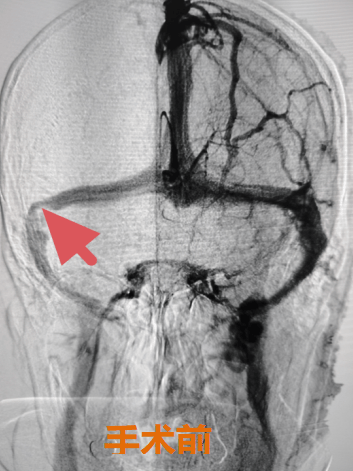

78 岁的郭奶奶被右侧 “搏动性耳鸣” 整整困扰了五年。近一个月来,耳鸣症状骤然加重,尤其在进餐时,耳边持续的 “咚咚” 声让她无法正常进食,日渐消瘦的身体与紧锁的眉头道出了无尽苦楚。更令人揪心的是,